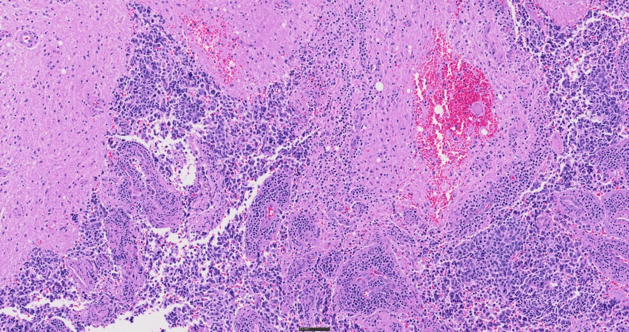

H&E 염색 조직, 40X

최대 여섯 가지 고성능 X Line™ 대물렌즈를 지원하고 True Color LED 조명과 색상 보정 카메라 프로파일을 사용하는 SLIDEVIEW VS200 시스템은 선명한 전체 슬라이드 이미지를 제공합니다. 이 스캐너는 샘플과 염색 특성을 일관적으로 재현하도록 설계되어 재스캔의 필요성을 최소화하고 효율적인 진단을 지원합니다.

명시야, 편광, 형광, 암시야, 위상차의 다섯 가지 이미징 모드를 사용하고 여러 기법을 단일 스캔에 조합하여 샘플에서 더 많은 세부 정보를 발견하세요. 이러한 유연성은 일상적 병리학부터 암 조직의 복잡한 세포 특성 분석까지 조직학 및 세포학 샘플을 관찰할 때 다양한 가능성을 열어 줍니다.